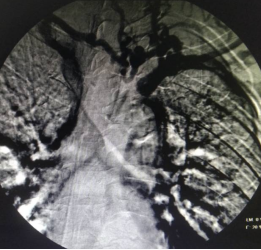

血液净化中心医生制定了内瘘结扎方案,把人为建立血流回心的“高速公路”封堵,DSA引导下穿刺上腔静脉置入一根23cm的长期透析导管,手术难度很大。

这一技术由四川大学华西医院崔天蕾教授首创,安岳县人民医院是四川省内第一家开展这一技术的县级医院。

DSA下行血管造影+上腔静脉穿刺+置入长期透析导管手术过程(白色粗箭头所指用经皮血管穿刺套件进行上腔静脉穿刺过程)